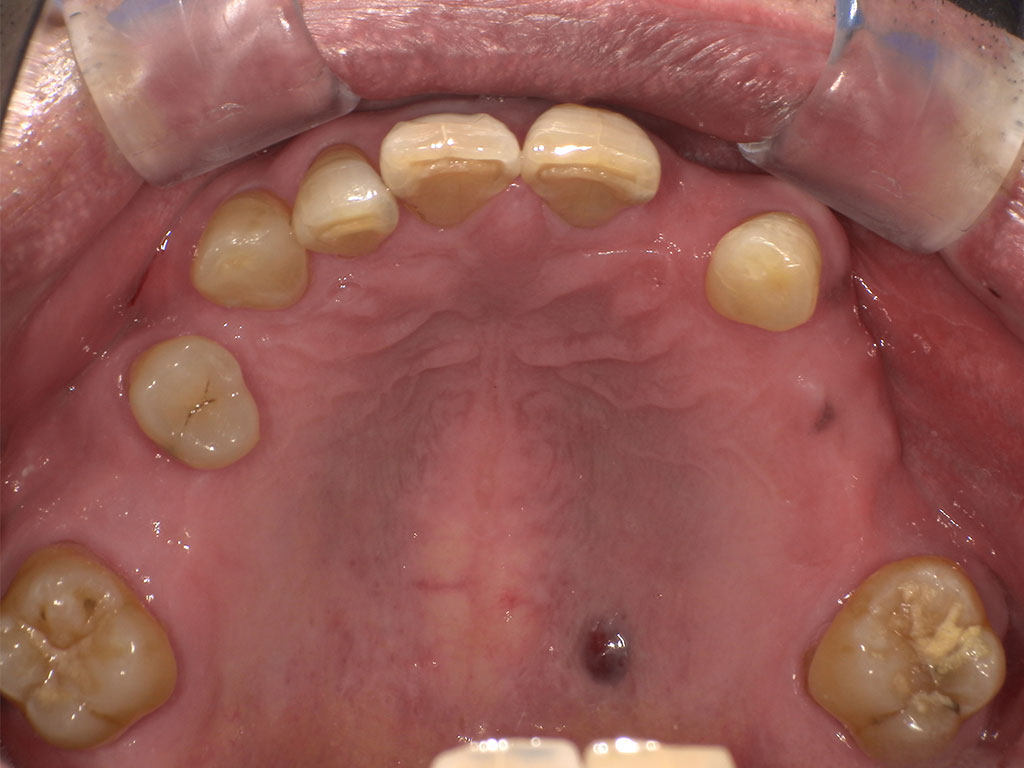

Before2

上顎右6番左2456番の欠損を補うスマイルデンチャー(Sing)

70代男性。上顎右6番左2456番が欠損した状態で来院。今まで使用していた保険の入れ歯を使用しているが滑舌が悪く不満があるため、インプラント手術も怖いということで自費の入れ歯をご希望とのこと。下顎の入れ歯については以前から使用していたもので問題ないとのこと。

金属部分がない、フィット感がある、入れ歯を支える歯への負担を軽減させるため、上顎右6番左2456番の欠損を補うスマイルデンチャーを作成